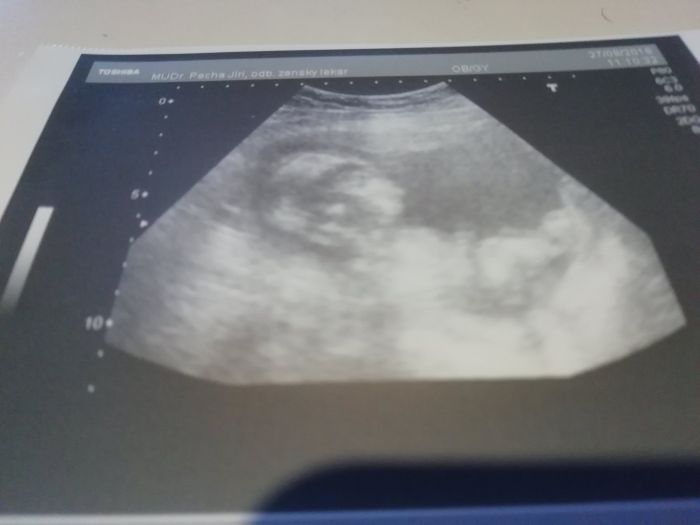

Autor: Pauky 27.8.2018 v 13:19

Tak kontrola v poradku, akorat nejak nevim, kolik merime. Ptala jsem se na pohlavi, ale my porad spime :)